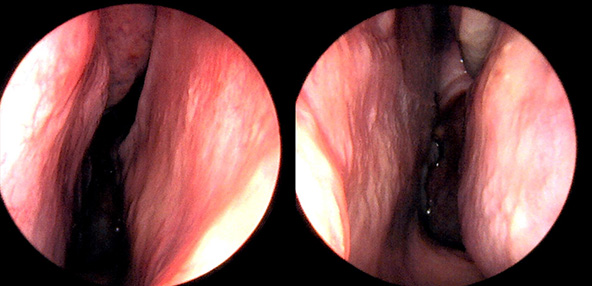

본 사진은 의료기관에서 진료를 본 환자이고, 전후 사진 인물이 동일인이며,동일조건에서 촬영이 되었습니다.